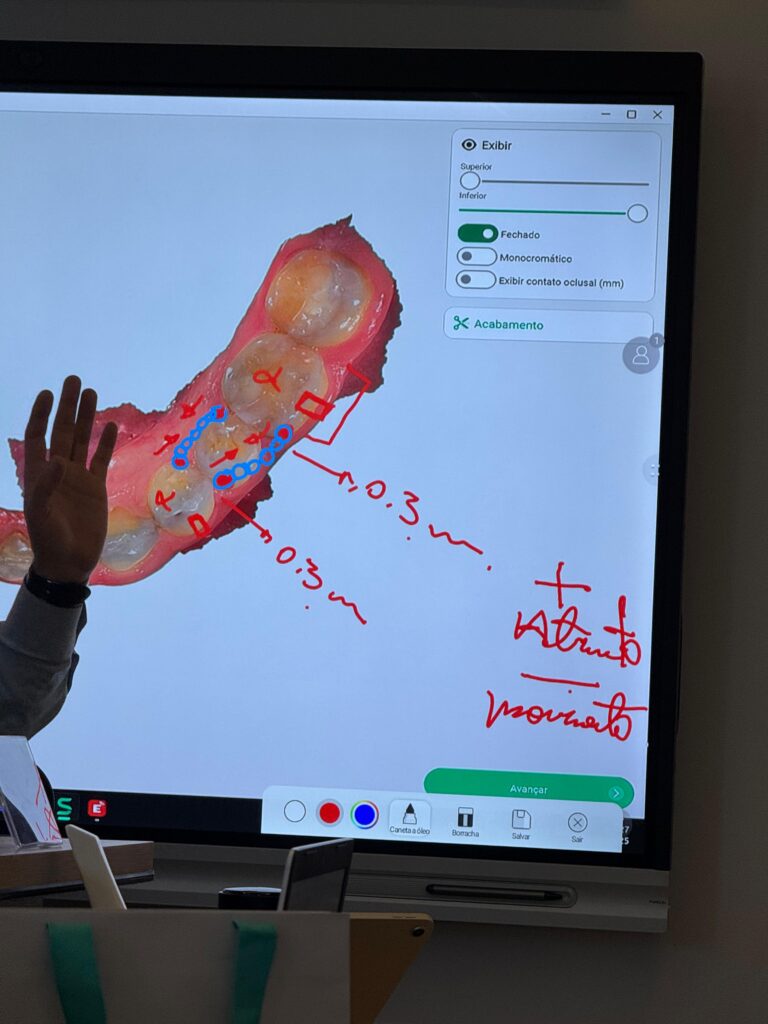

09:30 – Biomecânica aplicada ao uso de mini implantes: princípios de ancoragem esquelética

10:50 – Planejamento tridimensional: regiões seguras de inserção (maxila e mandíbula), planejamento digital e guias cirúrgicos

08:30 – Dispositivos associados aos mini implantes: MARPE, cantilever, distalizadores, elásticos, intrusão, retração e expansão

14:00 – Hands-on Parte 2: montagem de dispositivos associados (MARPE, distalizadores, cantilevers)

08:30 – Casos clínicos comentados: estratégias de escolha do dispositivo certo para cada tipo de movimento